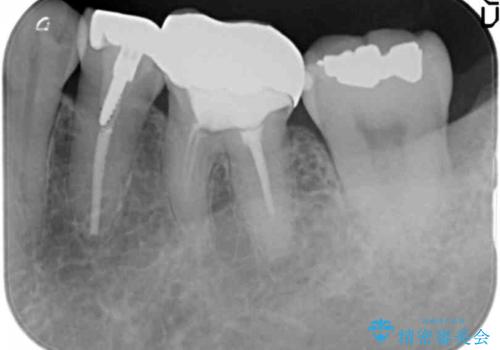

左下5番は根管治療のやりなおし、左下6番は上物(クラウン)のやり替えのみを行いました。

- 44万円(内訳 左下7:emaxプレスインレー 左下6:仮歯、ジルコニアクラウン 左下5:精密根管治療再治療、ファイバーコア、仮歯、ジルコニアクラウン)費用は治療当時の料金となります